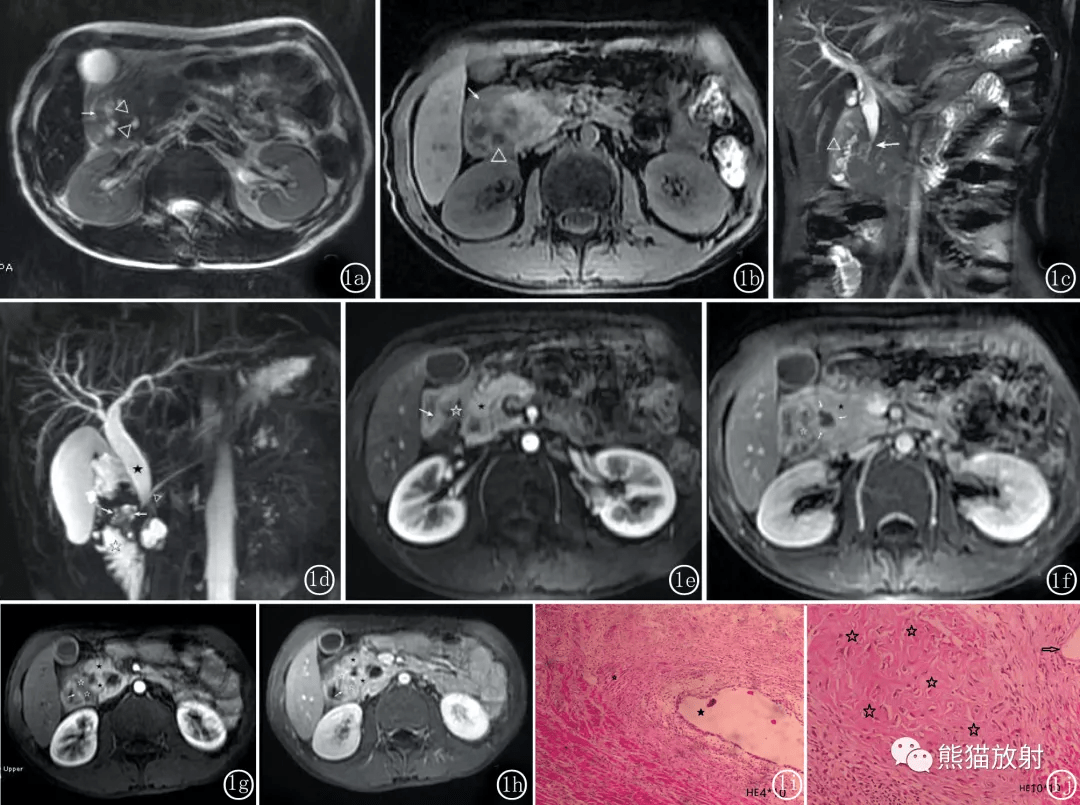

同一患者MRI图像 。

图1a.1 b 横断位T2WI 及T1WI 显示胰头增大并于十二指肠( ↑) 分界不清 , 可见十二指肠内侧多发小囊变 区( △)。

图1c 冠位T2WI 显示囊变( △) 及胆总管胰腺段狭窄( ↑)。

图1d MRCP 清晰显示多发囊变( ↑)。

图1e~1h 不同层面增强动脉期及延时期( 5min) 图像 , 显示完整的十二指肠内侧壁( ↑) 以及沟槽区延时强化的纤维瘢痕( ☆)。

图1f ( ↑) 显示囊壁延时强化 。

图1i ( HE 4 %uD7 10) : 显示肌样组织增生( 白星号) 、扩张的胰腺导管及增生的导管上皮( 黑星号)。 图1j ( HE 10 %uD7 10) : 显示病变内大范围纤维化( 白星号), 及扩张导管( 白箭)